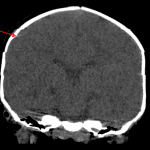

- Small focus of linear hyperdensity subjacent to the fracture site is favored to reflect streak artifact, though evaluation of this area is mildly limited by motion and surrounding streak artifact

Small focus of linear hyperdensity subjacent to the fracture site is favored to reflect streak artifact, though evaluation of this area is mildly limited by motion and surrounding streak artifact. No large acute intracranial hemorrhage.